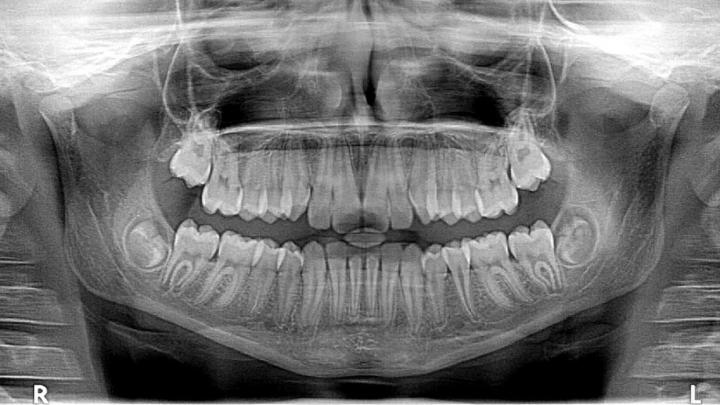

«В первую очередь это функциональная диагностика — рентген, фоторегистрация и другие аналогичные исследования. Она позволяет выявить особенности строения суставов челюстей и наметить правильный план лечения», — подчеркивает Ксения Мандровская.